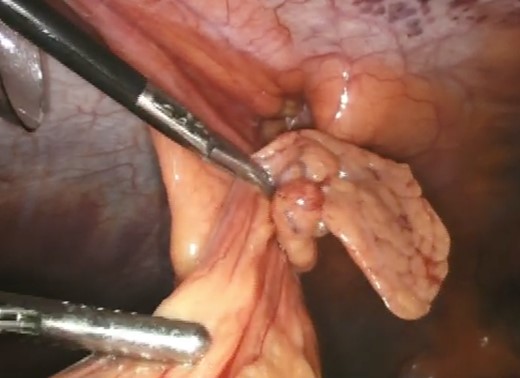

Upon successful reduction (Fig. 4), the hernia neck was closed laparoscopically with an intra-corporeal V-loc™ suture (Fig. 5). Closure of the hernia neck creates muscle apposition thus allowing for effective functioning of the abdominal wall musculature (Fig. 5). We extrapolated this data from incisional herniorrhaphy and the component separation technique [4]. The hernia defect was then covered with an underlay Ventralite™ mesh and secured with Absorbatac™ staples (Fig. 6). The Ventralite™ mesh is a dual layer mesh with one side consisting of an absorbable hydrogel barrier facing the bowel which reduces the risk of bowel adhesions. Her post-operative recovery was uneventful and she was discharged home the same day.

Laparoscopic intra-corporeal suturing of hernia neck with V-loc™ suture.